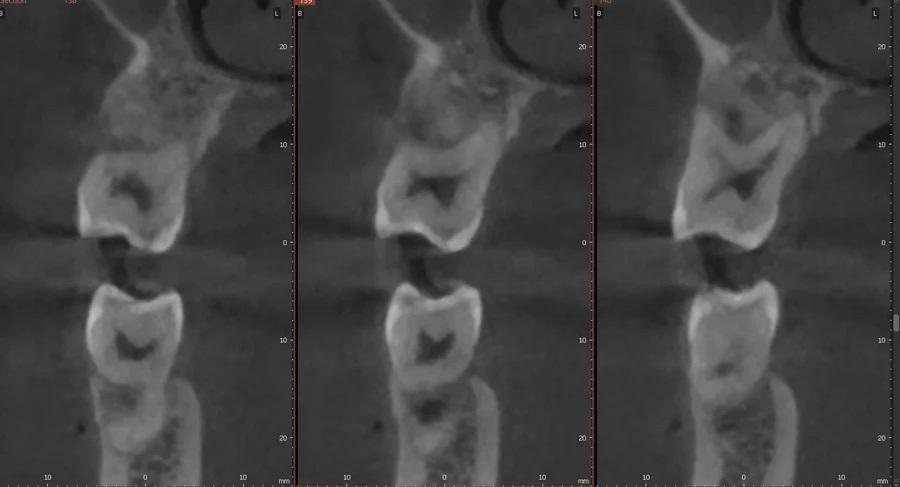

Фото 4. Предоперационное КЛКТ-исследование, указывающее на глубокую фуркацию, распространяющуюся на щечную поверхность небного корня зуба № 2.6, отсутствие щечной компактной пластинки и вестибулярное смещение с лингвальным торком корня.